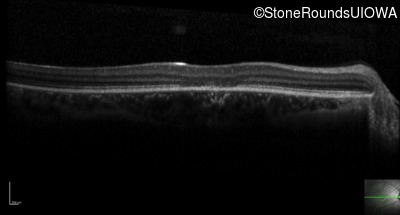

Optical Coherence Tomography - Left - 20/25 +2

Exemplar / OCT Stack

OCT Stack